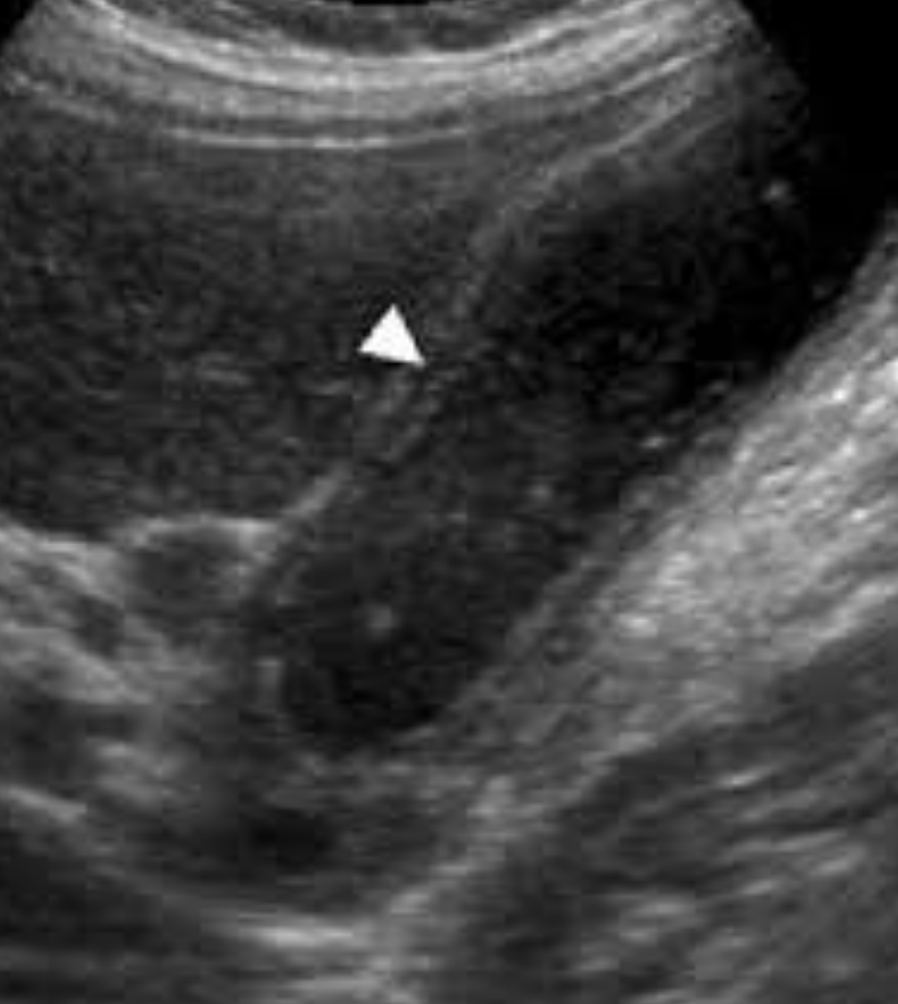

Diagnóstico de la colecistitis:

• USG: engrosamiento de la pared de la vesícula, signo del riel

¿A partir de cuánto se consdiera inflamación de la pared de la vesícula?

> 4 mm